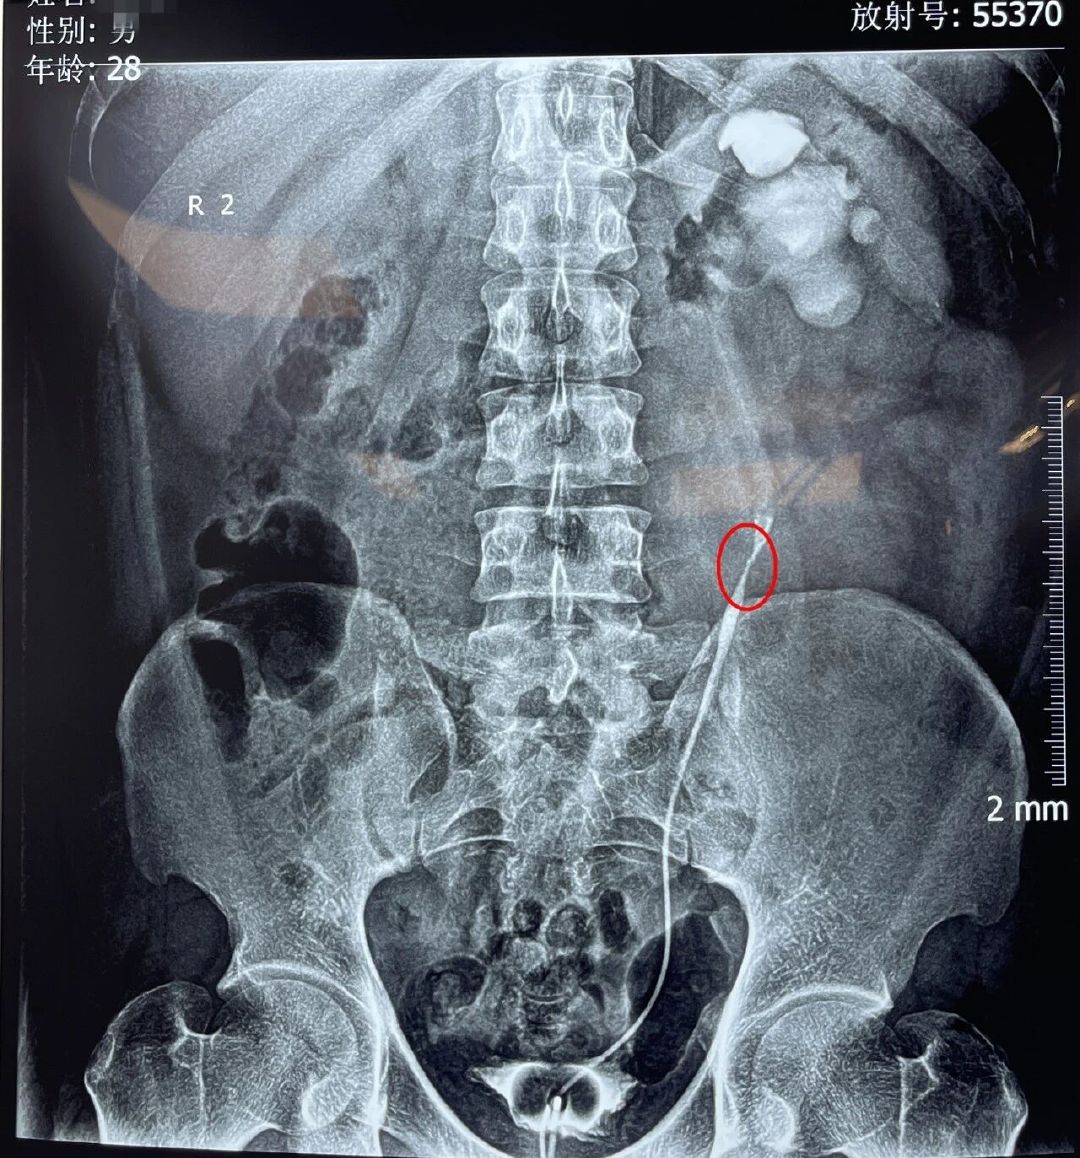

窗外阳光明媚,但28岁的潘先生却怎么也高兴不起来,看着手中的检查结果,他面露凝重:“你看我这个检查结果:肾功能重度损伤、左输尿管上段狭窄、左输尿管上段结石、左肾重度积水、右肾结石、泌尿系感染……,我这十来年,也不知道做那么多次体外碎石是为什么呢,问题没解决,还越来越严重。”

患者左侧输尿管锁闭段长约10毫米

“患者入院时,双肾都检查出结石,且左输尿管狭窄、局部闭锁,左侧输尿管上段结石,尿液排不出去,潴留在肾脏形成积水,肾功能重度损伤,手术难度较大。”云南结石病医院泌尿外科黄鸿宾主任表示:“如不能得到及时有效的治疗,肾积水会把他的肾实质像气球一样越撑越薄,直到失去肾功能,这些无法疏通的尿液也会渐渐滋生细菌,出现肾脏积脓、萎缩、坏死,甚至发生尿毒症危及生命。”

为确保手术万无一失,黄鸿宾主任进行了全院MDT会诊,采用了“经尿道输尿管镜下左输尿管导管置入术+经腹部左输尿管上段结石取出、狭窄段切除、端端吻合术”的综合手术方案,解除了潘先生的输尿管梗阻和结石问题,最大限度保护了其现有的肾脏功能。